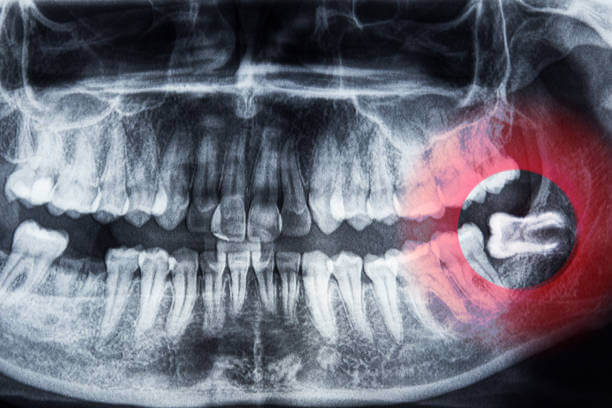

사랑니는 대부분 치아 뒤쪽에 위치해 제대로 자라지 못하고 염증, 충치, 잇몸질환 등을 유발합니다. 이럴 경우 건강보험 적용이 가능하며, 일부는 실손의료보험(실비보험) 청구도 가능합니다.

• 매복 사랑니 발치로 잇몸 절개, 골삭제, 봉합이 필요한 수술코드가 발생한 경우

• 통증·염증 등의 질병 사유로 인해 발치가 의학적으로 필요한 경우